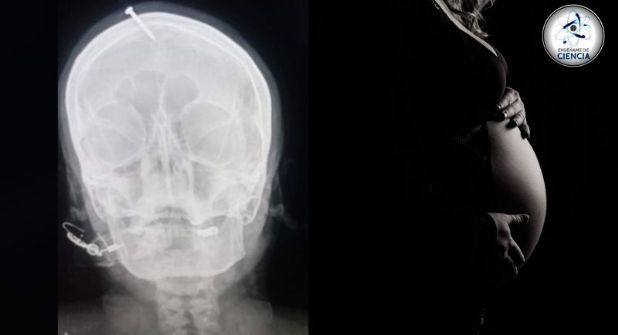

Hay algunos ritos tradicionales en cualquier cultura para asegurar un buen parto para las futuras madres, incluso promesas físicas para asegurar a un niño al momento del parto. Esto mismo hizo un curandero cuando martilló un clavo en la cabeza de una mujer embarazada para darle un hijo varón.

Fue así como el pseudo experto comenzó a introducir un clavo por la cabeza de su paciente, llegando poco a poco hasta adentro de su cabeza. Luego de sufrir intensos dolores, la implicada acudió al centro médico de Peshawar para retirar el objeto metálico, del cual había fallado para quitar de su sistema.

Tras examinar a la mujer embarazada se determinó, gracias a un escáner, el lugar el clavo del curandero, el cual fue enterrado en el cráneo sin llegar afortunadamente al cerebro.